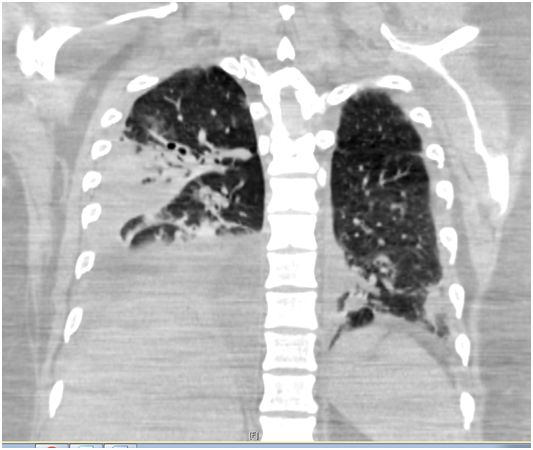

CT Thorax was arranged which confirmed right sided abscess/cavity. The case was discussed with thoracic surgeons who advised to manage conservatively & USS guided chest drain was put in under antibiotics cover. Meanwhile his bronchial washings grew Staphylococcus aureus (Panton valentine leucocidin positive). It was sensitive to Flucloxacillin. Case was discussed in multidisciplinary team meetings with microbiologist who advised to continue with 4 weeks of Flucloxacillin.

CT thorax showing bilateral consolidation and effusions more on right side and cavitatory lesion at right lung base.